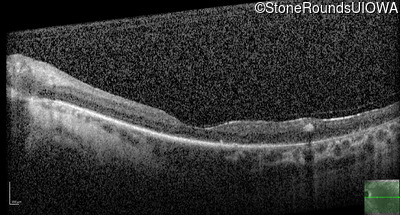

Optical Coherence Tomography - Left - 20/80 -2

Exemplar / OCT Stack